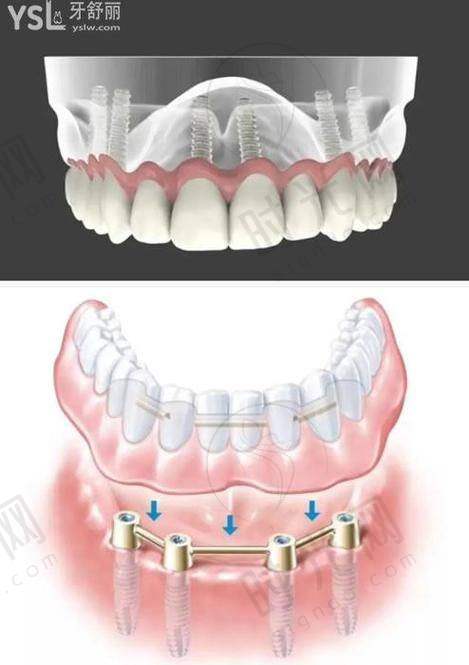

1. 成效真相:徐州口腔医院开展了多种种植牙技术,像常规种植、all - on - 4、all - on - 6等。收费6500的种植牙,大概率能为咱们提供比较稳定的牙齿修复成效。常规种植技术相对成熟,能较好地修复牙齿的咀嚼功能和外观。如果是all - on - 4或者all - on - 6技术,可能在半口或者全口牙齿缺失的修复上更有优势,能让咱们更快地修复正常的饮食和生活。而且,种植牙能避免传统假牙带来的不舒适感和稳定性差的问题,就像给咱们的口腔装上了一颗“真牙”。

1. 徐州口腔医院:徐州口腔医院开展多种种植牙技术,像常规种植、all - on - 4、all - on - 6等,技术较为全方面。收费6500元的种植牙在其收费区间内比较适中。虽然医生信息文档未提及,但作为当地有名的口腔医院,技术有一定的保护。而且医院开展的口腔治疗项目丰富,能为咱们提供一站式的口腔服务。

2. 徐州美奥口腔:这是一家正规私立连锁牙科,设有“MCIC复杂病例种植中 心”,擅长微创种植牙,种植体导航技术,all on four全口种植即刻负重,翼板区种植技术。医生团队有汪龙河、窦方伟、惠希琪等。韩国奥齿泰种植牙5500元起/颗,价格和徐州口腔医院6500元的种植牙有一定的可比性。这里种牙技术好,服务便捷,患者体验佳,是徐州牙科医院排名前十。

3. 徐州正博口腔医院:作为二级专科口腔医院,设立了无菌手术室,有着复杂病例种植中 心如穿颧穿翼种植、all - on - 4半口全口即刻种植技术。医生有王勇、李明等。韩国进口种植牙2980元起,韩国美格真种植牙4899元/颗等多种种植牙价格可供选择。以可靠医疗技术和优质服务在淮海经济地区享有较高声誉,设备高端,消毒严格,价格透明。